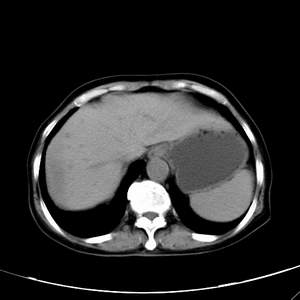

患者,女性,77岁,右上腹胀痛月余。afp正常。ca125升高。即往无肝炎病史。

肝右叶病灶是胆管细胞癌吗?门静脉右支癌栓形成?右侧肾上腺有问题吗?

快进快出符合肝癌表现

病灶强化不均匀,形态欠规整.患者年龄很高.

考虑肝癌

延时后,病变与肝脏呈等密度,先考虑:肝血管瘤.

最后5幅图片是延时7分钟的。门静脉右前支内有充缺吗?如有,肝血管瘤不好解释。

渐进性强化,中间见沙砾样钙化,首先考虑血管瘤

病灶渐进性向心性强化,延时病灶中心见条片状高密度影,局部见肝包膜回缩征,结合病人无肝炎病史,考虑肝右叶胆管细胞癌,门脉右支癌栓形成。